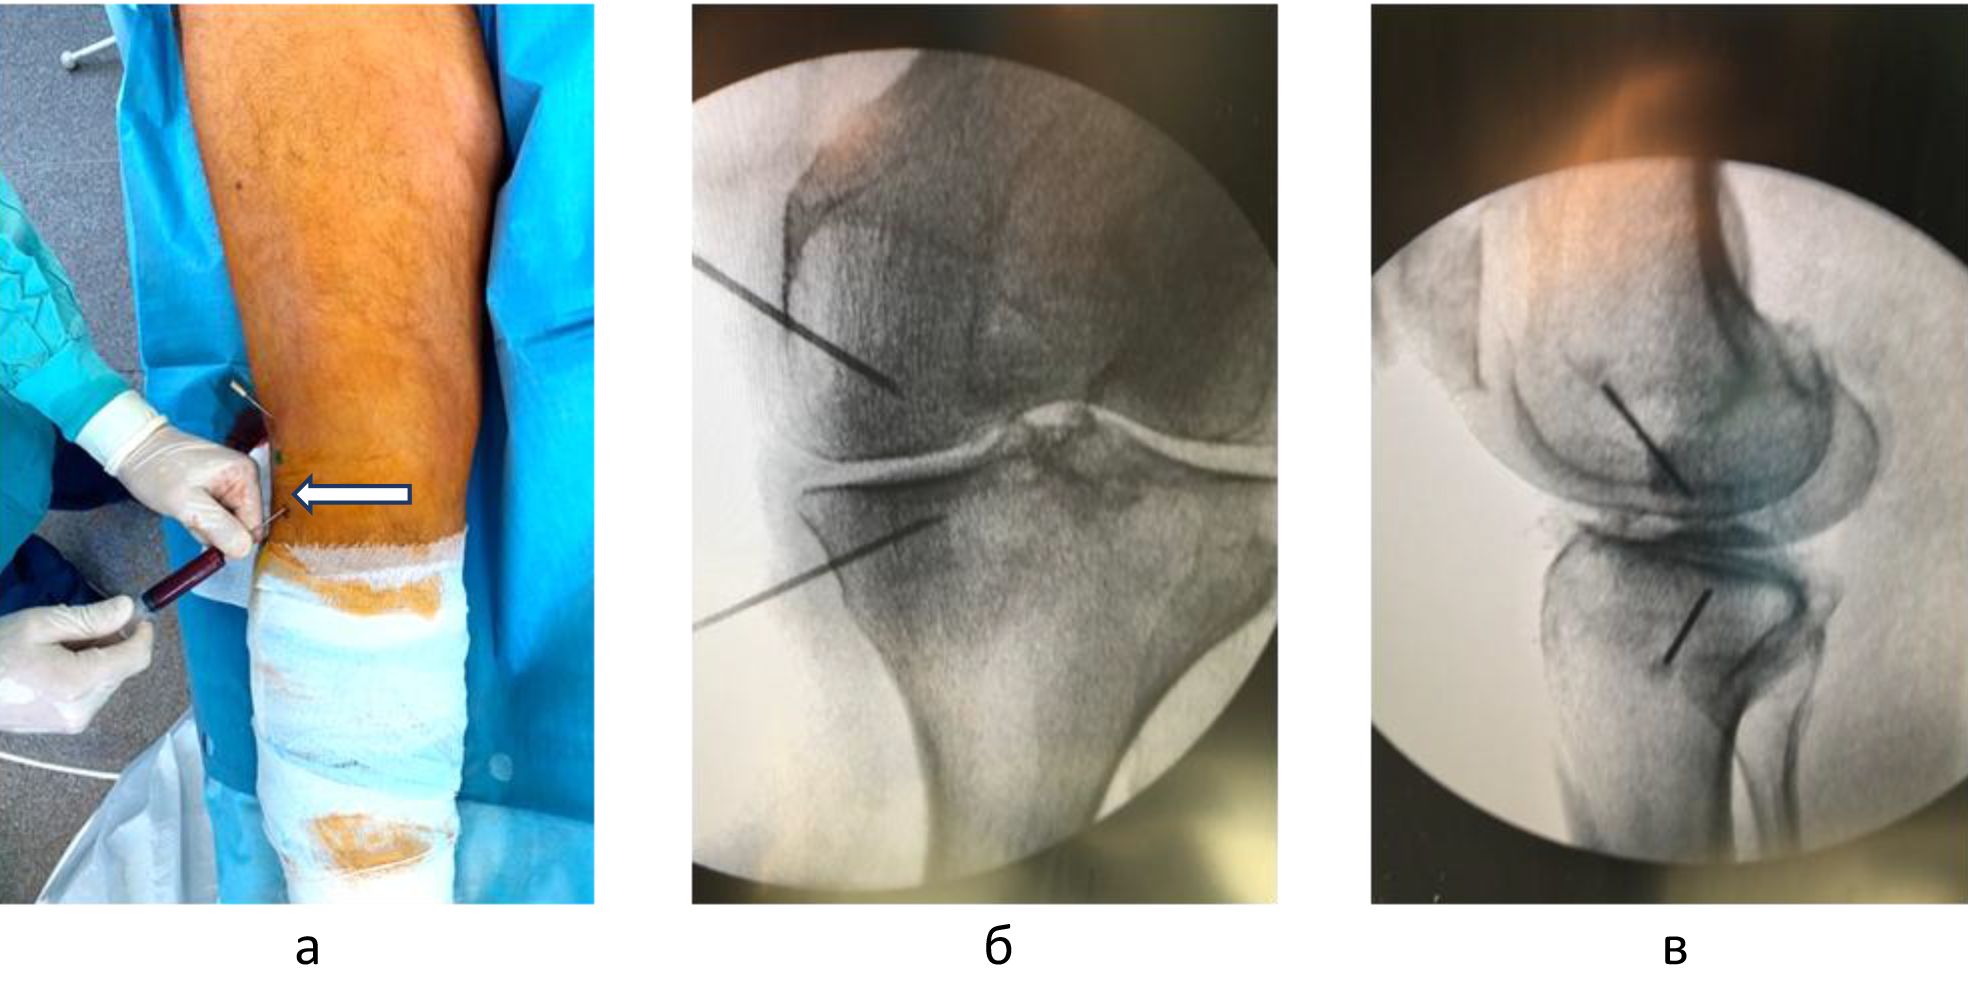

Для определения локализации и распространенности перегрузочного отека костного мозга всем пациентам выполняли МРТ. На Т1-взвешенных изображениях визуализировали снижение интенсивности сигнала, на Т2-взвешенных изображениях с жироподавлением и на коротких последовательностях «восстановления – инверсии» (STIR) выявляли высокую интенсивность сигнала (рис. 1).

Техника подготовки препарата и инъекции. Забор крови и приготовление ОТП выполняли в условиях процедурного кабинета или перевязочной при соблюдении необходимых правил асептики и антисептики. Согласно методике YCELLBIO PRP (Корея), двухкратно центрифугировали кровь пациента и получали 3 мл ОТП, которую центрировали в узком перешейке пробирки и забирали при помощи шприца (рис. 2) Количество тромбоцитов в готовом препарате составляло 962 ± 40 × 109/л.

Забор аспирата костного мозга и получение его концентрата осуществляли в операционной или перевязочной. В положении пациента лежа на спине или на боку, несколько кзади от передней верхней ости по ходу гребня подвздошной кости, проводили инфильтрацию мягких тканей до контакта иглы с серединой кортикальной площадки гребня 2%-м раствором лидокаина. Далее, используя троакар Jamshidi (11G), вращательными движениями проникали сквозь кортикальную пластинку на глубину 30–50 мм. После чего выполняли забор аспирата костного мозга в объеме 30 мл. Причем во время забора костного мозга изменяли направление острия троакара в толще губчатой кости с целью минимизации попадания цельной крови пациента в шприц. Полученный аспират был смешан с 5 мл раствора гепарина и помещен в стерильные контейнеры для дальнейшего сепарирования. Центрифугирование осуществляли согласно оригинальной методике (патент РФ № 2763250) при скорости 2400 об./мин длительностью 20 мин. После разделения костного мозга на фракции, одна из которых с высоким содержанием мезенхимальных клеток, была извлечена при помощи шприца. Концентрацию мононуклеарных клеток, часть из которых представлена мезенхимальными, в готовом ККМ определяли методом проточной цитофлуометрии, применяя антитела к CD34, CD14, CD73, CD105, CD90.

Внутрикостные инъекции ККМ и ОТП выполняли в условиях операционной. Используя 2%-й раствор лидокаина, инфильтрировали мягкие ткани по внутренней или наружной поверхности коленного сустава на 2 см проксимальнее и на 2 см дистальнее уровня суставной щели. Троакары вводили в кость вкручивающими движениями под углом 45 градусов по отношению к оси конечности и продвигали на глубину 1,5 см, достигнув субхондральных структур. Позиционирование троакаров оценивали с помощь электронно-оптического преобразователя (ЭОП) в 2 стандартных проекциях (рис. 3).